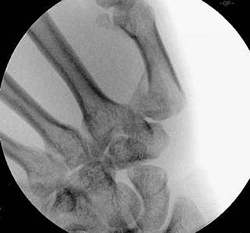

Basisfraktur des 1. Mittelhandknochen

Wenn die Frakturstellung nach Reposition und Ligamentotaxis

gut ist, kann die Fraktur mit einem gelenküberbrückenden Microfixateur

stabilisiert werde.

Die Frakturkontrolle muß in allen Ebenen kontrolliert

werden.